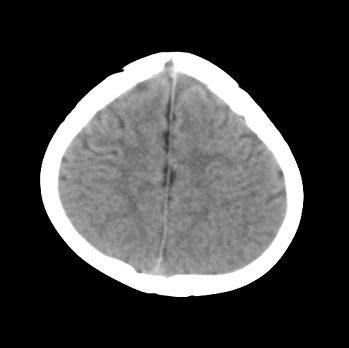

以下是引用22222222在2008-6-9 21:03:00的发言:[br]病灶周围见脑组织包绕,上部可见等或稍高密度壁环绕,壁且见小点钙化-----考虑皮样囊肿或表皮样囊肿可能,但侧脑室颞角内病灶不排除.